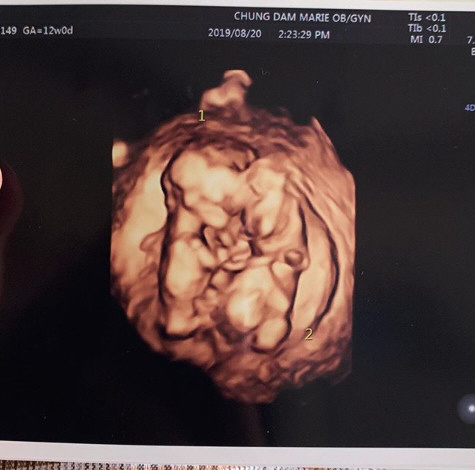

율희는 29일 자신의 인스타그램을 통해 "짱이의 쌍둥이 동생들 소식 듣고 많은 분들께서 축하해주셔서 너무 감사하다"라고 임신 축하에 화답했다. 이어 "요즘 입덧이 너무 너무 심해서 정신을 못 차리고 있는데 그만큼 그 누구보다 고생해주는 남편과 어머님 덕분에 별 탈 없이 행복하게 태교 중"이라고 밝혔다. 율희는 쌍둥이의 초음파 사진을 공개하며 "둥이들은 이렇게 서로 꼭 붙어 잘 크고 있다"고 덧붙였다. 최민환은 지난 16일 "여러분께 가장 먼저 들려 드리고 싶은 소식이 있다. 짱이의 동생이 생겼다"며 율희의 임신 소식을 알렸다.

둥이들은 이렇게 서로 꼭 붙어 잘 크고있답니다 다시한번 축하해주셔서 감사드려요